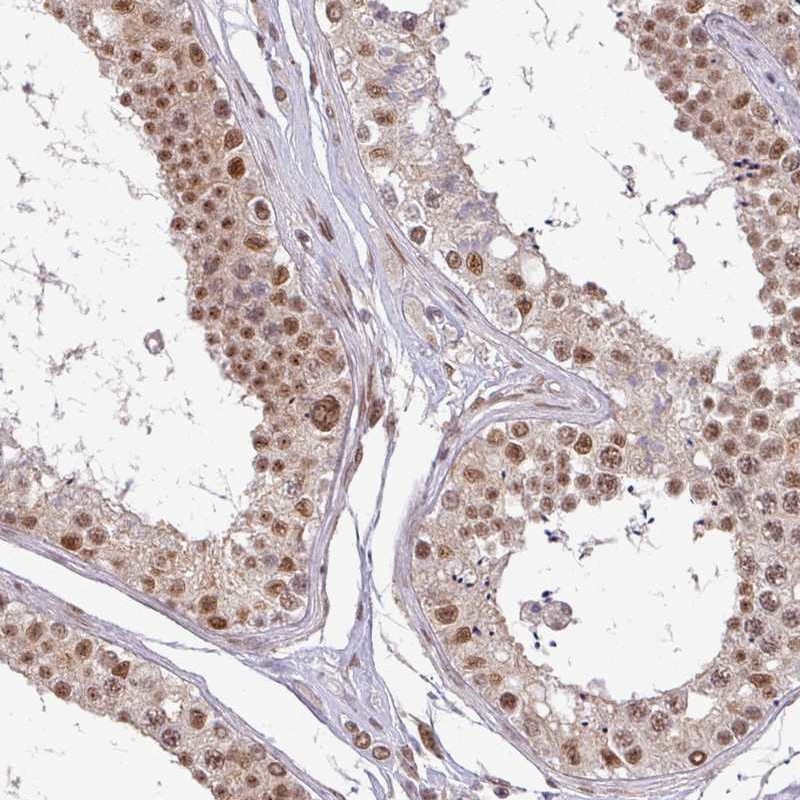

Immunohistochemical staining of human testis shows moderate nuclear positivity in cells in seminiferous ducts.